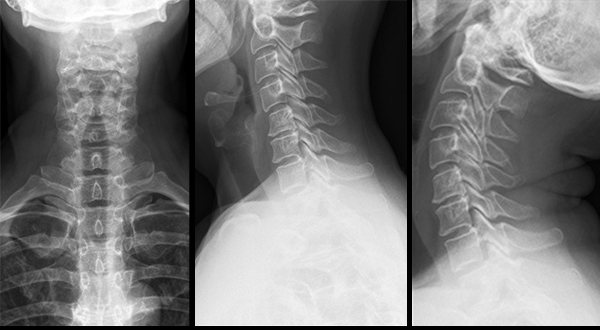

Подбор ортопедических подушек и матрасов проводится на основании обследований: рентгенограммы шейного, грудного и поясничного отдела позвоночника, УЗИ брахиоцефальных артерии, МРТ отделов позвоночника. Подбор подушек и матрасов проводит врач ортопед высшей категории, что гарантирует максимальный положительный эффект при применении выбранного изделия.

Основное инструментальное обследование, необходимое для диагностики патологии шейного отдела позвоночника и, как следствие - грамотного подбора подушки, является функциональная рентгенограмма шейного отдела позвоночника. Для поясничного и грудного отделов необходима боковая рентгенограмма в положении стоя.